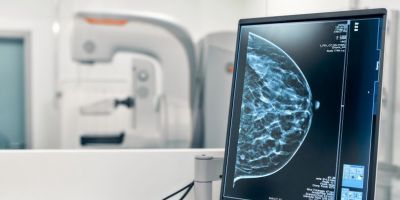

O Ministério da Saúde passou a recomendar o acesso a mamografia, via Sistema Único de Saúde (SUS), para mulheres de 40 a 49 anos – mesmo que não haja sinais ou sintomas de câncer de mama. De acordo com a pasta, a faixa etária concentra 23% dos casos da doença, e a detecção precoce aumenta as chances de cura.

Até então, a orientação era que o exame fosse feito a partir dos 50 anos.

A medida faz parte de um conjunto de ações anunciadas nesta terça-feira (23) voltado para a melhoria do diagnóstico e da assistência. A recomendação para mulheres a partir dos 40 anos é que o exame seja feito sob demanda, em decisão conjunta com o profissional de saúde.

As mamografias via SUS em pacientes com menos de 50 anos, de acordo com a pasta, representam 30% do total, o equivalente a mais de 1 milhão apenas no ano de 2024.

Outra medida anunciada é a ampliação da faixa etária para o rastreamento ativo – quando a mamografia é solicitada de forma preventiva a cada dois anos. A idade limite, até então, era 69 anos. Agora, passa a ser 74 anos. Dados do ministério revelam que quase 60% dos casos de câncer de mama estão concentrados entre 50 e 74 anos.

“A ampliação do acesso à mamografia aproxima o Brasil de práticas internacionais, como as adotadas na Austrália, e reforça o compromisso em garantir diagnóstico precoce e cuidado integral às mulheres brasileiras. O câncer de mama é o mais comum e o que mais mata mulheres, com 37 mil casos por ano”, reforçou a pasta.

Os números mostram que, em 2024, cerca de 4 milhões de mamografias para rastreamento e 376,7 mil exames diagnósticos foram realizados no SUS.